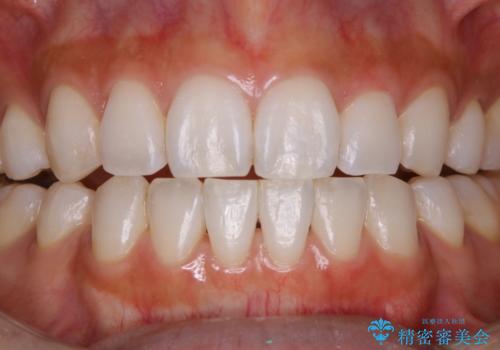

60分のPMTCで歯の黄ばみをきれいに除去

- 年末年始と忙しく、なかなか歯のケアがしっかりできなかった事と着色も気になるとのことで来院されました。PMTC60分コースを行いました。

歯科医院にて定期的に適切な処置を行うことが大切です。